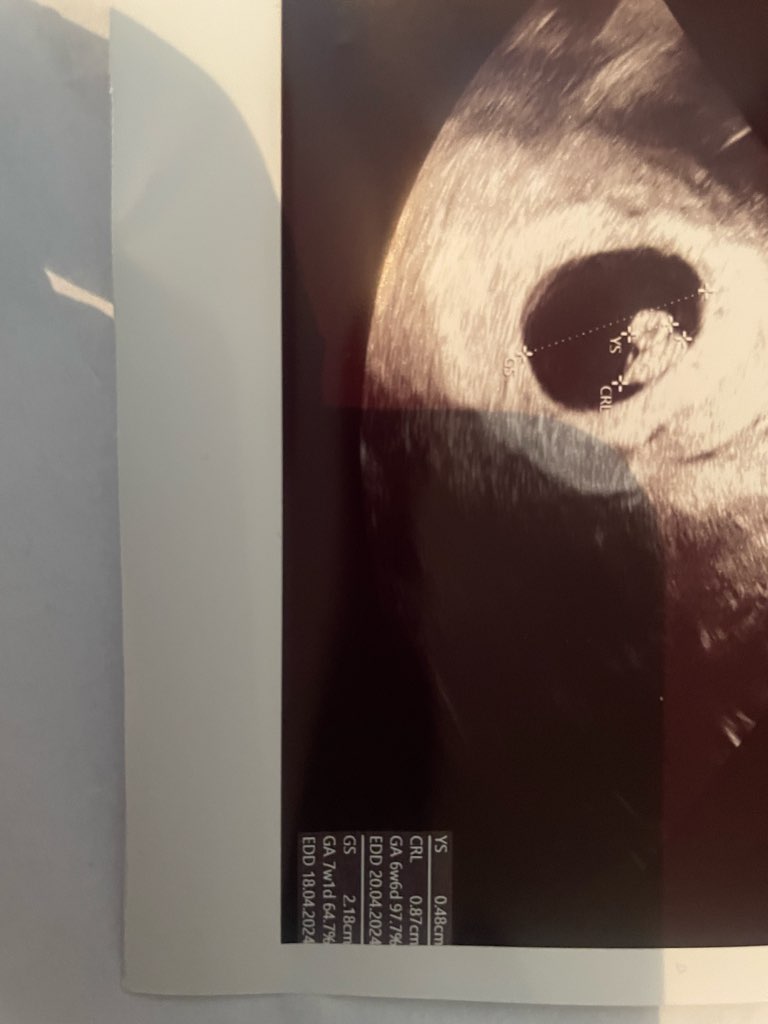

a wstaw zdjęcie usg jak to u Ciebie wyglada? Jest sam zoltkowy czy jest już zarodek ?ma już 0,48 cm. Boje się zeby nie urósł za duży. W poprzedniej ciąży która niby wszystko Ok w 6+2 był 0,36cm, a w 7+4 już 0,80cm. Generalnie powyżej 0,70cm zazwyczaj zoltkowy wskazuje na wady genetyczne zarodka i kończy się złe wiec teraz się stsresuje zwłaszcza ze już ten wymiar wydaje się być wiekszy niż wtedy w podobnym czasie..

jest zarodek i serce, ale w poprzedniej ciąży tez było.a wstaw zdjęcie usg jak to u Ciebie wyglada? Jest sam zoltkowy czy jest już zarodek ?

tak widać wszystko ładnie. Ale jeszcze do 7mm jest daleko w sumie i na razie jest to norma. Ciężko stwierdzić jak to się skonczy ale trzymam kciuki żeby już większy nie rósł i żeby było ok. Kiedy masz kolejna wizytę ?Wyraźne ?